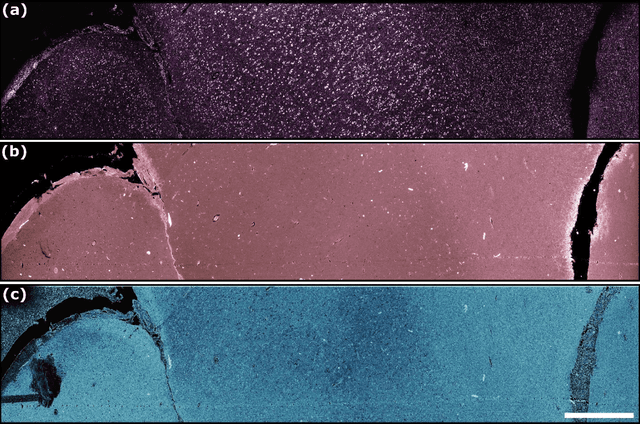

Abstract:Modern histopathology relies on the microscopic examination of thin tissue sections stained with histochemical techniques, typically using brightfield or fluorescence microscopy. However, the staining of samples can permanently alter their chemistry and structure, meaning an individual tissue section must be prepared for each desired staining contrast. This not only consumes valuable tissue samples but also introduces delays in essential diagnostic timelines. In this work, virtual histochemical staining is developed using label-free photon absorption remote sensing (PARS) microscopy. We present a method that generates virtually stained histology images that are indistinguishable from the gold standard hematoxylin and eosin (H&E) staining. First, PARS label-free ultraviolet absorption images are captured directly within unstained tissue specimens. The radiative and non-radiative absorption images are then preprocessed, and virtually stained through the presented pathway. The preprocessing pipeline features a self-supervised Noise2Void denoising convolutional neural network (CNN) as well as a novel algorithm for pixel-level mechanical scanning error correction. These developments significantly enhance the recovery of sub-micron tissue structures, such as nucleoli location and chromatin distribution. Finally, we used a cycle-consistent generative adversarial network CycleGAN architecture to virtually stain the preprocessed PARS data. Virtual staining is applied to thin unstained sections of malignant human skin and breast tissue samples. Clinically relevant details are revealed, with comparable contrast and quality to gold standard H&E-stained images. This work represents a crucial step to deploying label-free microscopy as an alternative to standard histopathology techniques.

Abstract:The field of histology relies heavily on antiquated tissue processing and staining techniques that limit the efficiency of pathologic diagnoses of cancer and other diseases. Current staining and advanced labeling methods are often destructive and mutually incompatible, requiring new tissue sections for each stain. This prolongs the diagnostic process and depletes valuable biopsy samples. In this study, we present an alternative label-free histology platform using the first transmission-mode Photon Absorption Remote Sensing microscope. Optimized for automated whole slide scanning of unstained tissue samples, the system provides slide images at magnifications up to 40x that are fully compatible with existing digital pathology tools. The scans capture high quality and high-resolution images with subcellular diagnostic detail. After imaging, samples remain suitable for histochemical, immunohistochemical, and other staining techniques. Scattering and absorption (radiative and non-radiative) contrasts are shown in whole slide images of malignant human breast and skin tissues samples. Clinically relevant features are highlighted, and close correspondence and analogous contrast is demonstrated with one-to-one gold standard H&E stained images. Our previously reported pix2pix virtual staining model is applied to an entire whole slide image, showcasing the potential of this approach in whole slide label-free H&E emulation. This work is a critical advance for integrating label-free optical methods into standard histopathology workflows, both enhancing diagnostic efficiency, and broadening the number of stains that can be applied while preserving valuable tissue samples.

Abstract:In the past decades, absorption modalities have emerged as powerful tools for label-free functional and structural imaging of cells and tissues. Many biomolecules present unique absorption spectra providing chromophore-specific information on properties such as chemical bonding, and sample composition. As chromophores absorb photons the absorbed energy is emitted as photons (radiative relaxation) or converted to heat and under specific conditions pressure (non-radiative relaxation). Modalities like fluorescence microscopy may capture radiative relaxation to provide contrast, while modalities like photoacoustic microscopy may leverage non-radiative heat and pressures. Here we show an all-optical non-contact total-absorption photoacoustic remote sensing (TA-PARS) microscope, which can capture both radiative and non-radiative absorption effects in a single acquisition. The TA-PARS yields an absorption metric proposed as the quantum efficiency ratio (QER), which visualizes a biomolecules proportional radiative and non-radiative absorption response. The TA-PARS provides label-free visualization of a range of biomolecules enabling convincing analogues to traditional histochemical staining of tissues, effectively providing label-free Hematoxylin and Eosin (H&E)-like visualizations. These findings represent the establishment of an effective all-optical non-contact total-absorption microscope for label-free inspection of biological media.

Abstract:Histological images are critical in the diagnosis and treatment of cancers. Unfortunately, the current method for capturing these microscopy images require resource intensive tissue preparation that delays diagnosis for many days to a few weeks. To streamline this process, clinicians are limited to assessing small macroscopically representative subsets of tissues. Here, we present a combined photoacoustic remote sensing (PARS) microscope and swept source optical coherence tomography (SS-OCT) system designed to circumvent these diagnostic limitations. The proposed multimodal microscope provides label-free three-dimensional depth resolved virtual histology visualizations, capturing nuclear and extranuclear tissue morphology directly on thick unprocessed specimens. The capabilities of the proposed method are demonstrated directly in unprocessed formalin fixed resected tissues. Here, we present the first images of nuclear contrast in resected human tissues, and the first 3-dimensional visualization of subsurface nuclear morphology in resected Rattus tissues, captured with a non-contact photoacoustic system. Moreover, we present the first co-registered OCT and PARS images enabling direct histological assessment of unprocessed tissues. This work represents a vital step towards the development of a real-time histological imaging modality to circumvent the limitations of current histopathology techniques.